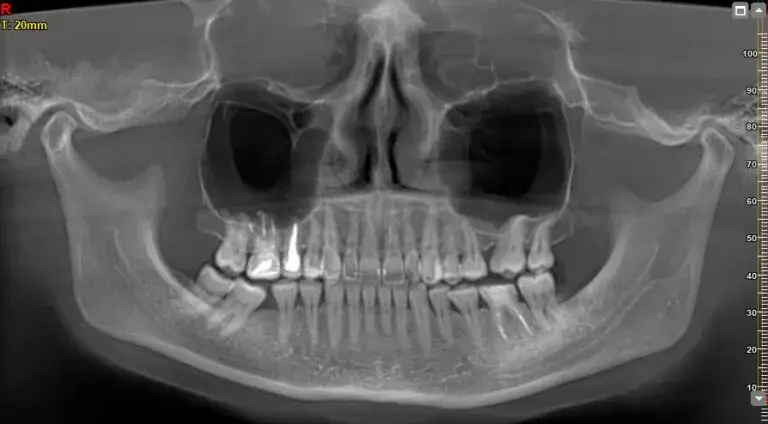

Uzyskanie pantomogramu na NFZ jest prostym procesem, ale wymaga spełnienia pewnych warunków. Po pierwsze, aby zrealizować to badanie, potrzebne jest skierowanie od dentysty z odpowiednią specjalizacją. Pantomogram jest dostępny dla dorosłych pacjentów, którzy są leczeni endodontycznie lub protetycznie. Warto pamiętać, że badanie to można wykonać raz na pięć lat, co oznacza, że jest to usługa, która może pomóc w długoterminowej diagnostyce.

Aby uzyskać pantomogram w ramach NFZ, niezbędne jest skierowanie od lekarza dentysty, który posiada odpowiednie kwalifikacje. Dentysta musi być specjalistą w dziedzinie stomatologii lub być w trakcie szkolenia specjalizacyjnego. Skierowanie powinno zawierać dokładne informacje dotyczące pacjenta oraz uzasadnienie, dlaczego badanie jest konieczne. Tylko wtedy pacjent może liczyć na pełną refundację kosztów badania.

W przypadku dorosłych pacjentów, pantomogram można wykonać raz na pięć lat, co jest istotne dla zachowania zdrowia jamy ustnej. Dzieci mogą natomiast korzystać z tego badania co trzy lata, o ile istnieją medyczne wskazania. To różnicowanie częstotliwości badań jest dostosowane do potrzeb różnych grup wiekowych i ich specyficznych wymagań zdrowotnych.

Pacjenci powinni być świadomi, że pantomogram na NFZ można wykonywać w różnych interwałach czasowych w zależności od grupy wiekowej. Dorośli pacjenci mają prawo do wykonania pantomogramu raz na pięć lat, co jest istotne dla monitorowania ich zdrowia jamy ustnej. Dzieci i młodzież w wieku od 5 do 18 lat mogą korzystać z tego badania co trzy lata, ale tylko w uzasadnionych medycznie przypadkach. Takie różnice w częstotliwości badań są dostosowane do potrzeb zdrowotnych różnych grup wiekowych.